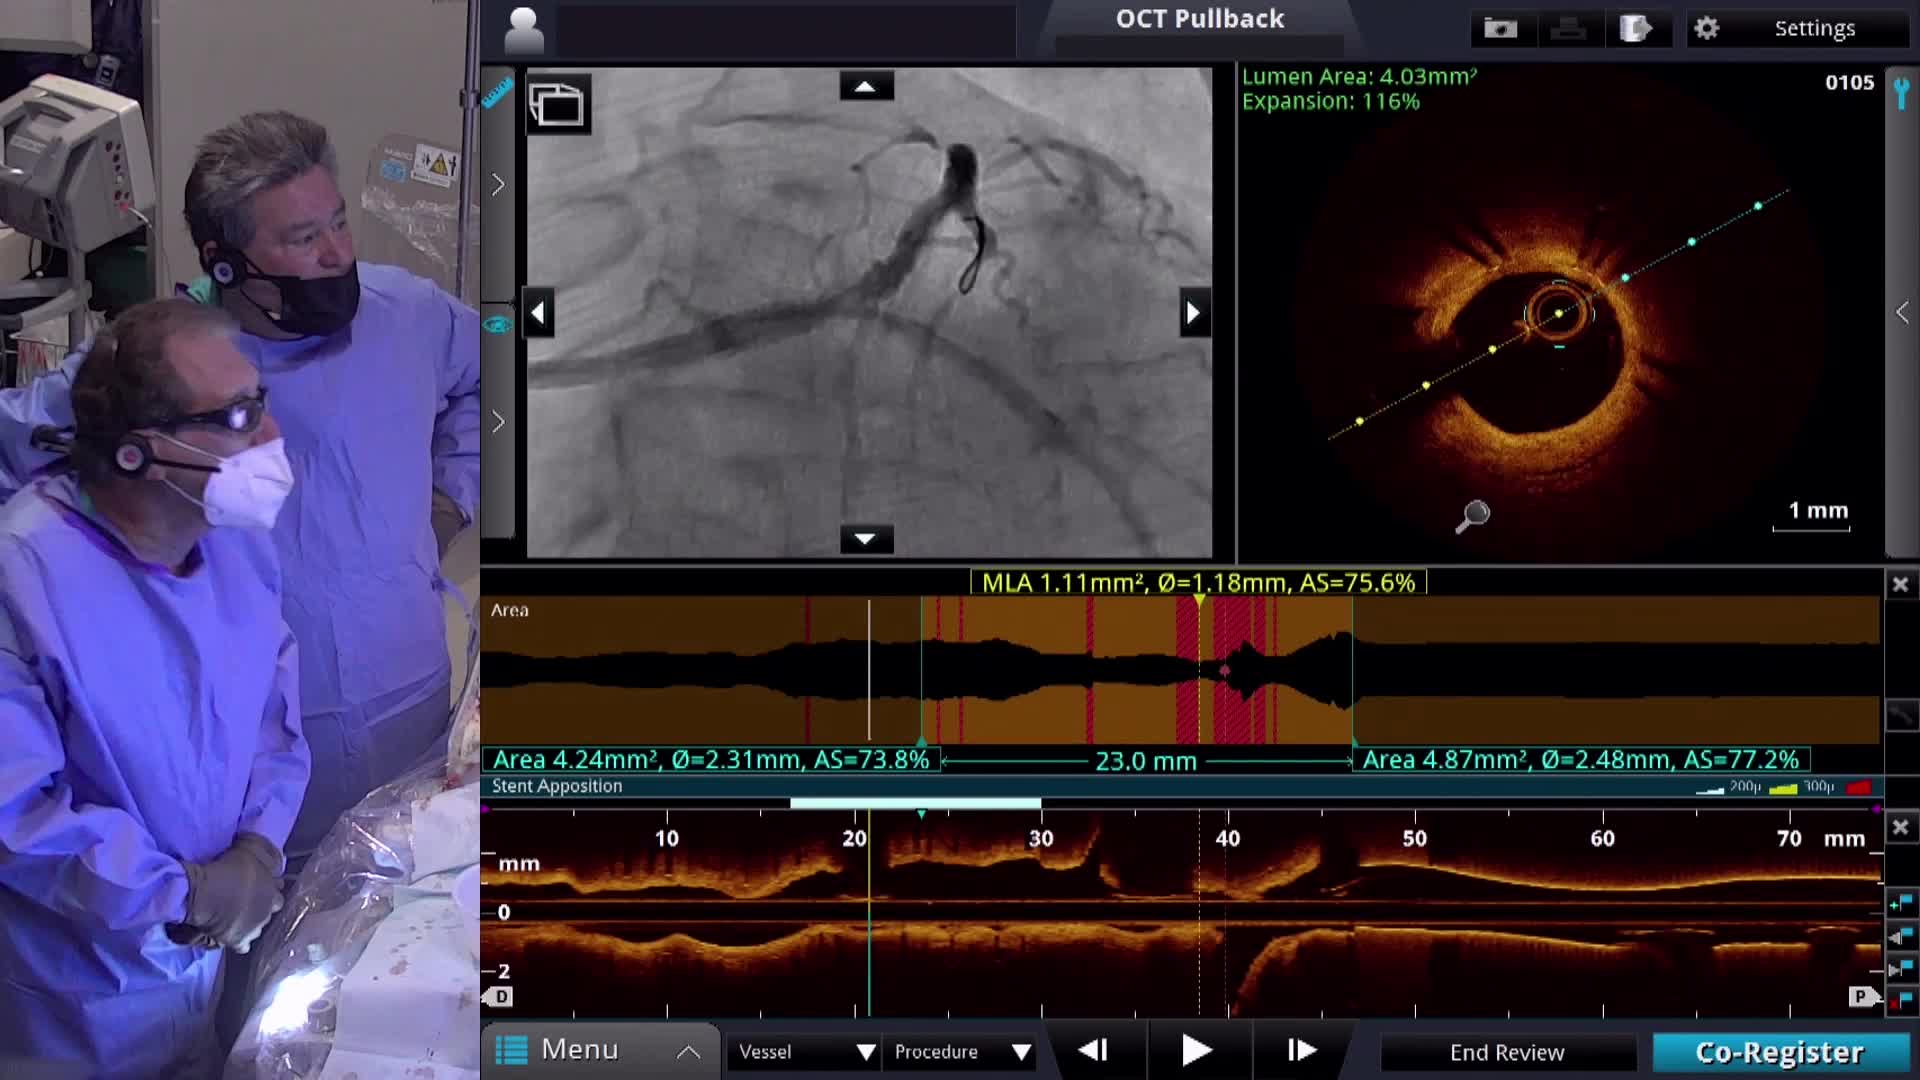

OPCI LIVE - Imaging Guided Treatment of Complex Bifurcation ISR Live Case and Panel Discussion

OPCI

OPCI LIVE - Left Main Bifurcation PCI with Mechanical Support for oLAD-oLCX with Severe In-Stent Restenosis (ISR) Secondary to Underexpansion